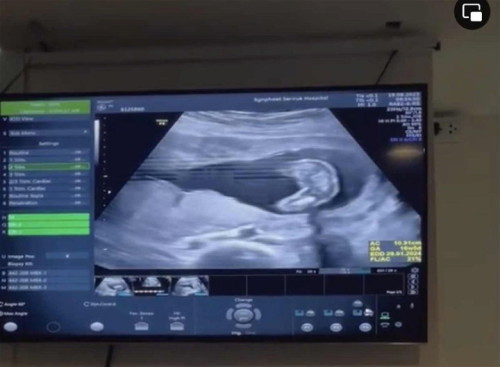

ท้อง 17W3Dแม่ๆรู้เพศยังคะ

สวัสดีค่ะ บ้านนี้ท้องได้ 17W3D วันนี้ไปหาลุงหมอมา ลุงหมอบอกยังไม่ชัว อาจจะเป็น ผู้หญิง แม่ๆรู้เพศกันตอนกี่สัปดาห์คะ แล้ว 17W3D ถ้าเป็น ผช. จู๋น้องจะโผล่ออกมายังคะ อิแม่ลุ้นมากๆเลยค่ะ ลูกคนแรก ผช คนนี้ ท้องสองค่ะ